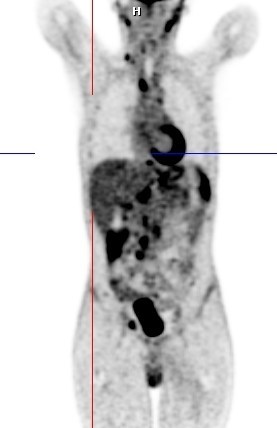

PREPARING MY PATIENT FOR F-18 FDG PET/CT STUDY